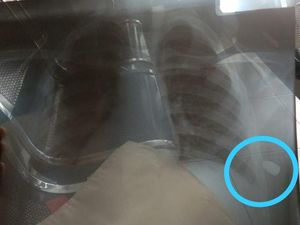

Seorang bocah laki-laki, IA (11) diduga menjadi korban peluru nyasar di Pademangan, Jakarta Utara. Peluru sempat bersarang di bagian punggung korban.

Proyektil peluru yang bersarang di punggung bocah IA (11) korban peluru nyasar, telah diangkat. Polisi kini tengah menyelidiki asal usul peluru tersebut.